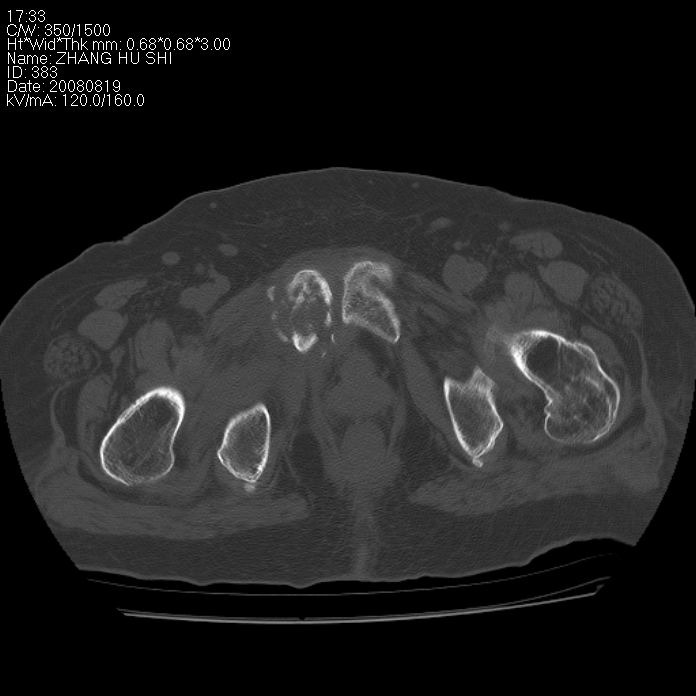

标题: CT15287:女 93岁 右髋关节疼痛 原左侧粗隆间骨折 CT发现右耻 [打印本页]

标题: CT15287:女 93岁 右髋关节疼痛 原左侧粗隆间骨折 CT发现右耻

支持转移并周围软组织侵犯右闭孔内肌侵犯,但tb不能完全除外。